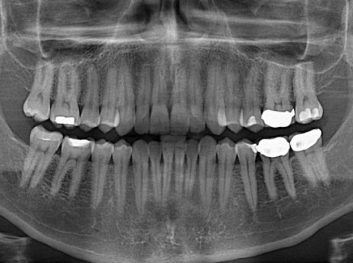

在體外測(cè)試中,材料刺激干細(xì)胞進(jìn)入牙本質(zhì)的增殖和分化速度,促進(jìn)形成牙齒骨組織。研究人員認(rèn)為,一旦材料在受損牙齒中應(yīng)用,這些干細(xì)胞可以自動(dòng)修復(fù)來自填充物上的損壞。在本質(zhì)上,該生物材料將使牙齒自愈。

在未來,Adam Celiz說,可再生材料能制成各種填充物以便受損牙齒的自身治愈,降低補(bǔ)牙失敗率,甚至?xí)蟛糠秩藢?duì)根管治療的需要。

這個(gè)研究團(tuán)隊(duì)今年還榮獲英國(guó)皇家化學(xué)學(xué)會(huì)(Royal Society of Chemistry)新興技術(shù)獎(jiǎng)材料類第二名。